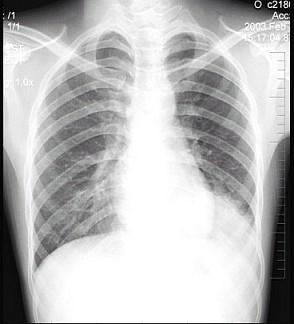

问题 男性患者,19岁,咳嗽、发热1周,X线检查如图,最可能的诊断是 ( )

选项 A.左下肺不张 B.左侧胸膜肥厚 C.左下肺炎症 D.左侧胸腔积液 E.左下支气管扩张

答案 C